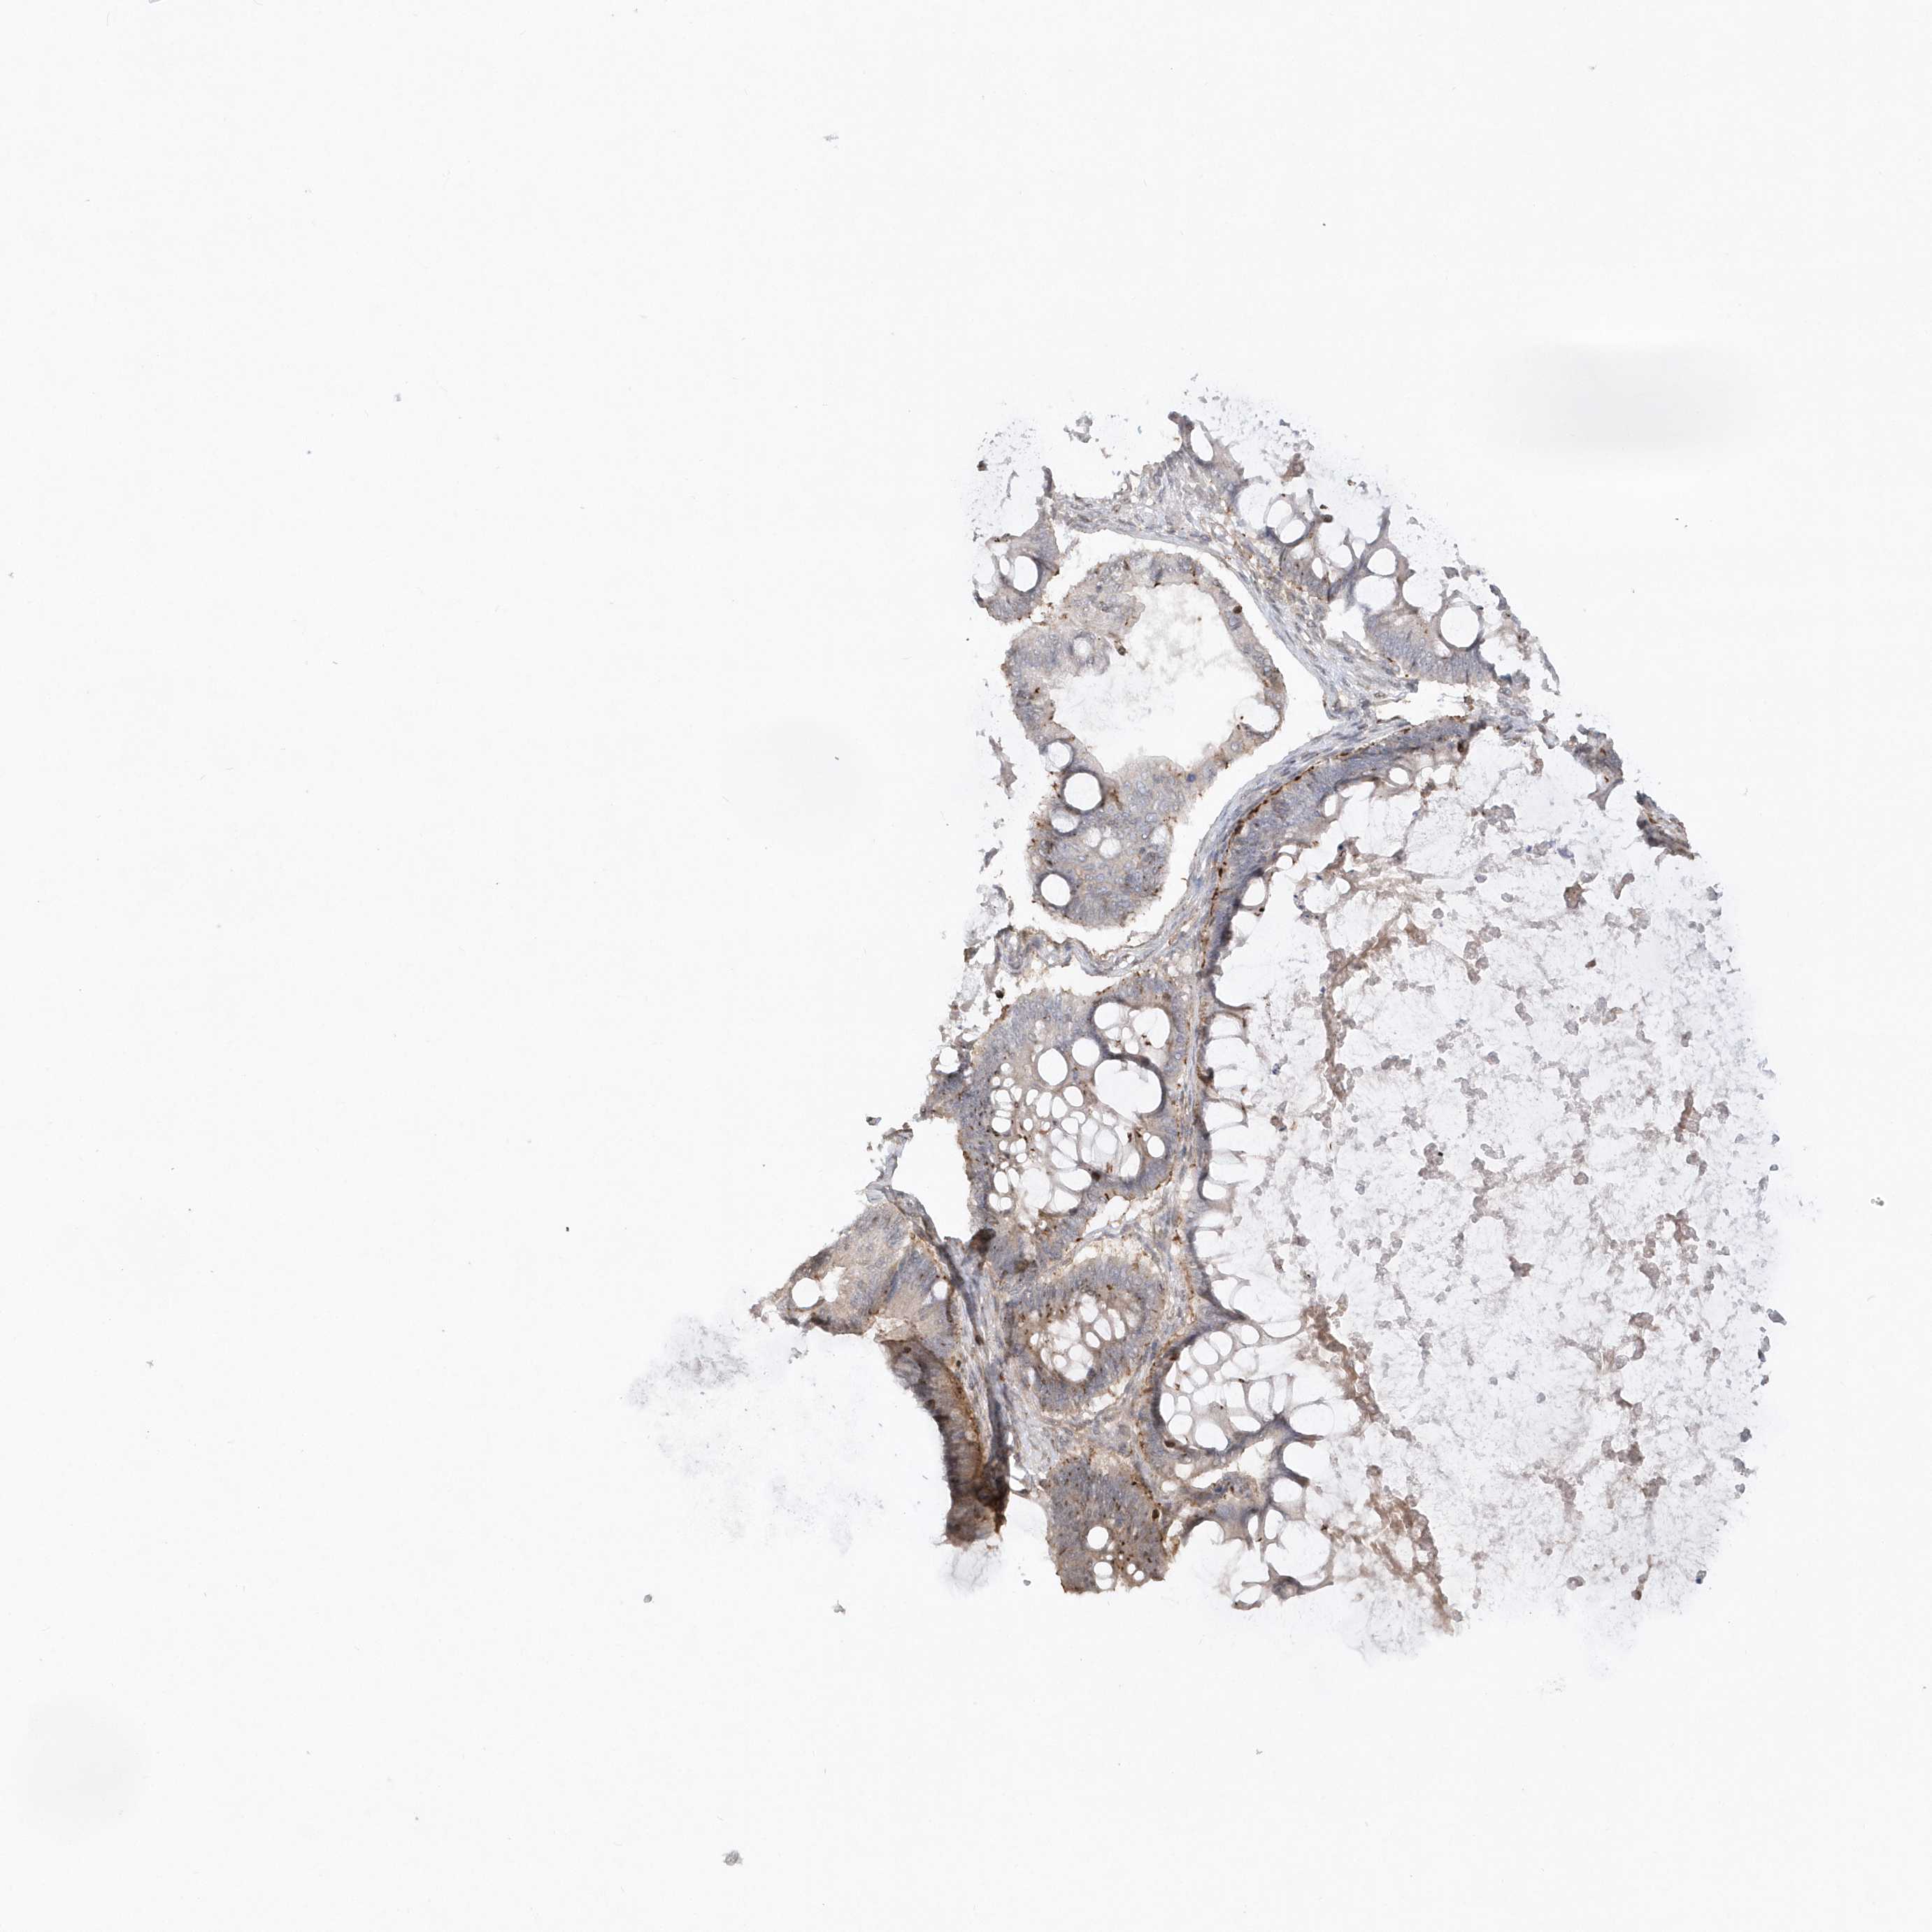

OVARIAN CANCER - Protein expressioni

A mouse-over function shows sample information and annotation data. Click on an image to view it in a full screen mode. Samples can be filtered based on level of antibody staining by selecting one or several of the following categories: high, medium, low and not detected. The assay and annotation is described here.

Note that samples used for immunohistochemistry by the Human Protein Atlas do not correspond to samples in the TCGA dataset.

Antibody stainingi

Antibody staining in the annotated cell types in the current human tissue is reported as not detected, low, medium, or high, based on conventional immunohistochemistry profiling in selected tissues. This score is based on the combination of the staining intensity and fraction of stained cells.

Each image is clickable and will lead to virtual microscopy that enables deeper exploration of all samples and also displays staining intensity scores, fraction scores and subcellular localization as well as patient and tissue information for each sample.

Antibody HPA034757

Staining

High

Medium

Low

Not detected

Intensity

Strong

Moderate

Weak

Negative

Quantity

>75%

75%-25%

<25%

None

Location

Nuclear

Cytoplasmic/membranous

Cytoplasmic/membranous,nuclear

Cystadenocarcinoma, serous, NOS

Carcinoma, endometroid

Cystadenocarcinoma, mucinous, NOS

Carcinoma, NOS